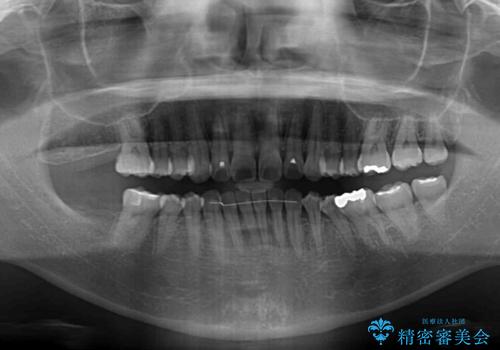

- 上下前歯の叢生を気にして来院された患者様です。

費用を抑え、期間もあまりかけずに治療をしたいとのことで、インビザライン・ライトを用いて矯正治療を行うこととしました。

インビザライン・ライトは、製作できるアライナーの枚数に制限があるため、移動可能な量に限りがあります。

一方で、半年から1年程度で治療を終えることができるため、軽度の歯列不正の患者様には大変お勧めです。